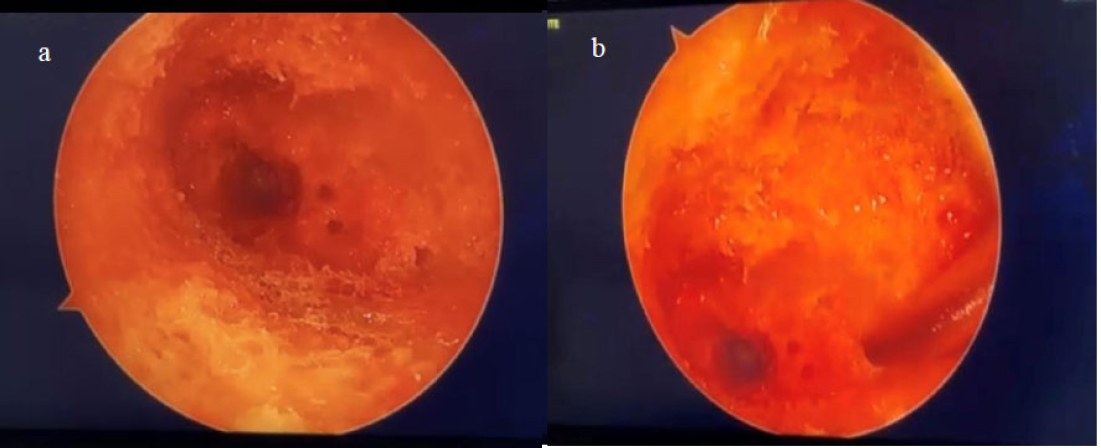

After one hour, the tetracycline-infused specimen displayed patchy yellowish-green fluorescence under UV light (Fig. 5, Supplementary Video 3).

Yellowish green calcification under ultraviolet (UV) light.

(Supplementary Video 3: Tetracycline labelling revealed yellowish green areas of calcification under ultraviolet light)

Alizarin Red staining produced orange deposits under green light illumination (Fig. 6, Supplementary Video 4). No regional dominance of labeling (superior vs. inferior) could be determined with either tetracycline or alizarin red dye.

Orange calcification deposits under green light.

(Supplementary Video 4: Alizarin red staining revealed orange calcification deposits under green light in the femoral neck)